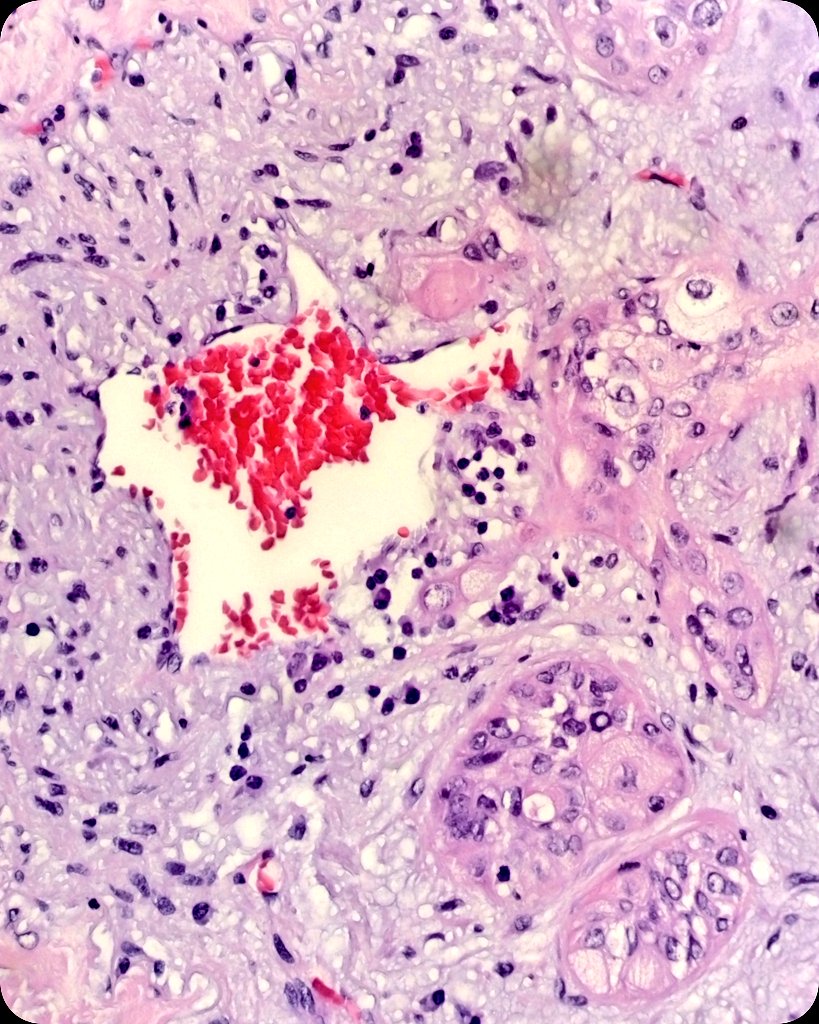

♂️ in his 80s. 🩺 Hemothorax ➕ pleural nodules. 💉 Pleural biopsy. 🔬 Angiosarcoma. IHC ➕ ERG, FLI1, D240, CD31. 3️⃣ #PINA2024 ➕ Reunión del grupo de trabajo de Patología Intervencionista de la SEAP-IAP. 🗓️ 27/04/24. Salón de actos del @HUCA.

♂️ in his 80s.

🩺 Hemothorax ➕ pleural nodules.

💉 Pleural biopsy.

🔬 Angiosarcoma.  IHC ➕ ERG, FLI1, D240, CD31.